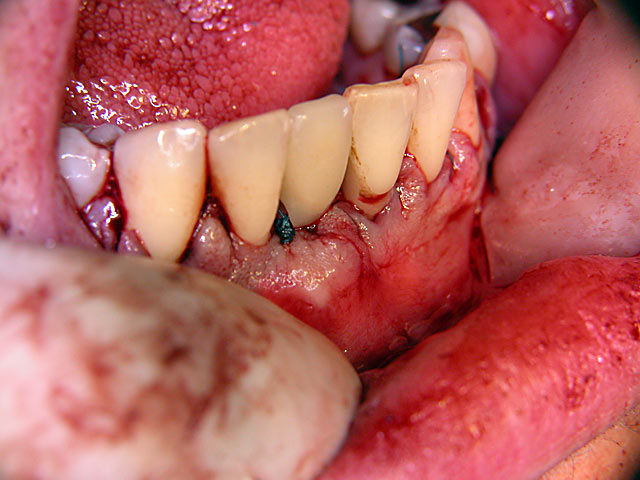

Sofort-Implantation: